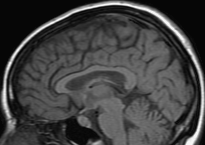

V-C Denoising of a magnitude MR knee image

We have also applied our CURE-LET denoising algorithms to an actual magnitude MR image of the knee. This 16-bit raw image has been acquired on a Siemens 1.5 Tesla Magnetom Sonata MR system, following a sagittal T2-weighted protocol. The standard deviation of the complex Gaussian noise has been estimated from a signal-free region of the squared data, as , and subsequently treated as known.

Fig. 11 shows the denoising results of the various CURE-LET algorithms. As observed, the noise is efficiently attenuated and the contrast is significantly improved, owing to a proper reduction of the signal-dependent bias introduced by the noise.